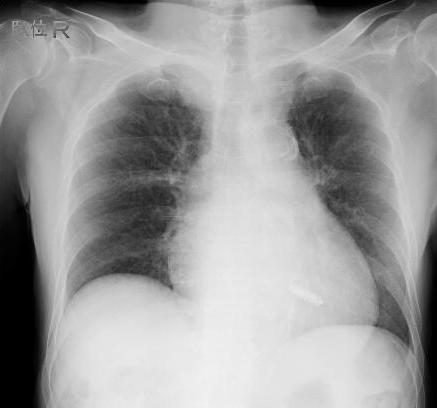

今回のリードレスペースメーカは、ポケットを作成する必要がなく、リードもありません。右室心室中隔心尖部に植込み、VVIRで、電池寿命も約10-14年、MRI対応のデバイスです。